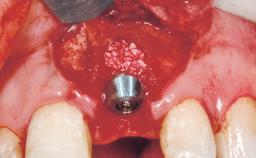

Immediate Flapless Placement of an Implant in a Maxillary Right Lateral Incisor Site

This 43-year-old male patient, a non-smoker, came to our practice because of a fracture of tooth 12 caused by a bicycle accident. Due to the combined para- and infrabony crown and root fracture, tooth extraction, and subsequent implant placement were suggested to the patient as the therapy of choice. The patient had high esthetic expectations with regard to the treatment outcome and asked for an immediate fixed provisional restoration. His individual esthetic risk profile summed up to a medium esthetic risk.

Placement Protocol Immediate implant placement

Tooth Site Maxillary incisor or canine

Socket Morphology Single-root socket

Socket Integrity Sufficient, with intact bone walls